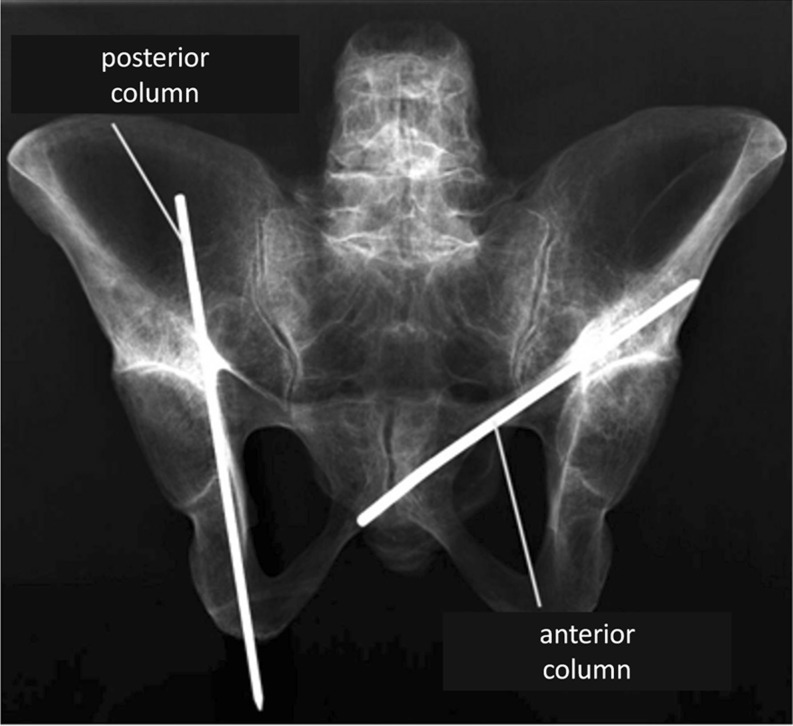

Using a 2.5-mm drill bit, a hole was made and one cannulated 6.5-mm lag screw was placed under direct vision by one experienced orthopaedic trauma surgeon. Screw placement was possible in all pelvises. No iatrogenic fracture was induced. One screw each was placed for posterior and anterior columns (Fig. 1). Optimal screw placement was achieved using direct visualisation and then immediately afterwards validated using C-arm image-intensified fluoroscopic imaging. Each specimen was therefore positioned on a radiolucent table, and anteroposterior (AP), iliac oblique and obturator oblique views were obtained. No violation of articular joint surface was tolerated. The cortex was penetrated at the antegrade and retrograde entry points only. In the literature, antegrade and retrograde placements are described for each column [2, 5–9]. Therefore, we assessed the relationship of both entrance points of each screw to surrounding structures. A randomised order for the different entry points was used when placing anterior or posterior column screws (Figs. 2, 3, 4 and 5).

Fig. 1.

Anteroposterior (AP) radiograph of a full pelvis specimen with both anterior and posterior columns addressed by one wire each for demonstration purposes